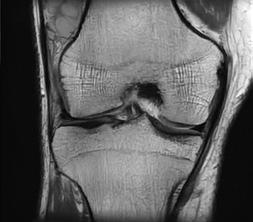

PD STIR - 1024 x 1024 matrix - 3mm slice thickness

Sag T2 - 0.5 x 0.5 min - 0:56 min Ax PD FatSat - 0.6 x 0.6 mm - 1:30 min Cor PD FatSat - 0.6 x 0.6 mm - 1:15 min Cor PD - 0.5 x 0.5 mm - 0:58 min © 2020 CANON MEDICAL SYSTEMS // MREU200040

Fast knee protocol with AiCE on Vantage Orian 1.5T

EasyTech Knee Package

The EasyTech Knee Package consists of the SUREVOI Knee and KneeLine+ applications and supports the operator in automatically centering the volume of interest (VOI) and position slices for knee examinations. The application also detects when the knee is incorrectly placed in the RF coil. It enables a knee examination with just one mouse click.

SUREVOI Knee

SUREVOI Knee is a positioning support function that automatically detects the knee and places the VOI and pre-saturation zones (if necessary) to eliminate wrap-around and flow artifacts. Using anatomical recognition, SUREVOI detects if the center of the knee and the center of the RF coil are aligned, and instructs the operator if repositioning is needed.

KneeLine+

KneeLine+ automatically defines the standard scan planes of the knee (axial, sagittal and coronal). If necessary, the orientation and position of the standard planes can be adjusted.